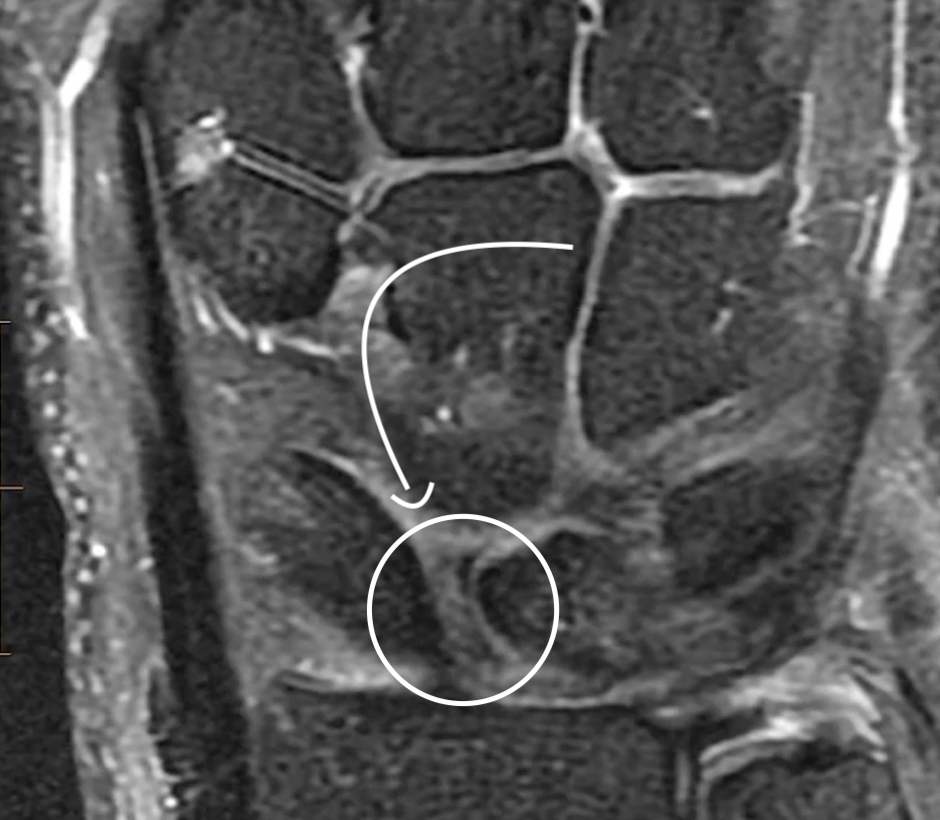

• Results in a lunate basically angulated volarly

• Look at angle below with green curved line

• Should be less than 60 deg, if >70 deg almost always DISSI